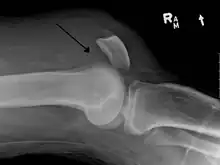

Quadriceps tendon rupture in plain X-ray